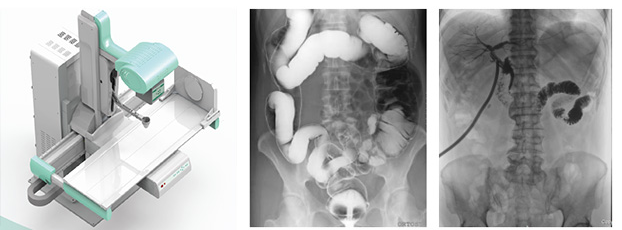

隨著現代醫療技術快速發展,傳統的X射線技術實現數字化,出現了多功能DR。多功能DR采用數字影像平板探測器取代傳統膠片,直接捕獲X線影像,并轉化為高清晰數字圖像,對比傳統的間接影像設備,多功能DR可以直接將X射線轉化成圖像,成像更清晰,放射劑量更小。

多功能DR大大提高了普通放射設備準確診斷的能力,為臨床創造了價值,它可以進行全身各部位的拍片、透視和點片攝影。接下來小編給大家介紹一下這三種模式的區別。

點片攝影是在透視的條件下,對病變部位進行可視化觀察,待發現疑似病變部位的時候進行瞬間點片,從而能夠準確獲取病變部位的高清影像用于臨床診斷,從而在一定程度上降低漏診誤診率。病人不動,通過選擇鍵由透視直接切換攝影的曝光過程。在透視過程中,保存一幅靜止的圖像。常用于消化道、膽系造影下的攝影等。它既可以觀察運動器官的運動功能,又能在有感興趣的圖像時,對膠片曝光保留感興趣的圖像,便于進一步診斷。